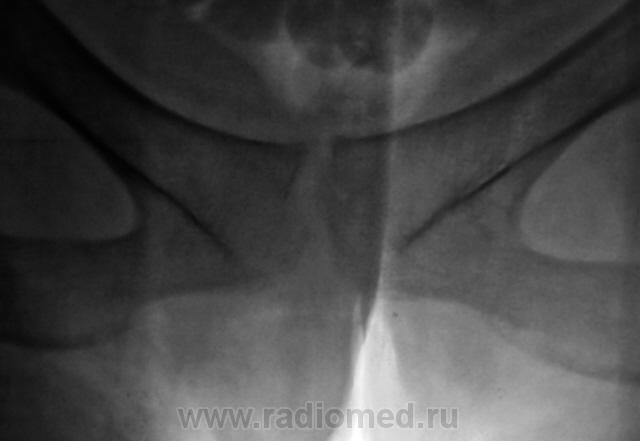

Возможно, перелом последнего копчикового тоже был?

303.p9030043-1_640x480.jpg304.p9030044-1_640x480.jpg

Поздно заметил ветку.. увидел симфизит, перелом остистого L4, мазоль Co 5, и  конечно spina bifida S1 ))) глянуть бы межпозвоночные..